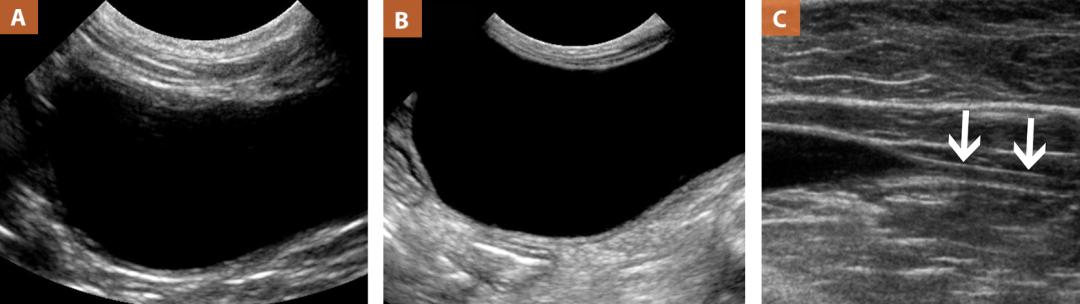

犬的肝脏(图1A)相对于邻近的脾脏呈低回声。犬体内的镰状脂肪不一定是反映肝脏整体回声的良好指标,因为相对于正常犬的肝脏,它可能表现为低回声、等回声或高回声。犬门静脉有明显的高回声壁。 图1所示:(A)犬肝脏长轴切面。肝脏的回声和回声正常,门静脉壁(高回声壁)和肝静脉(等回声壁)清晰。在远场区,肝脏颅周的曲线高回声线是反射的肺/膈-肝界面。(B)猫肝脏长轴切面。请注意近场的镰状韧带大的等回声脂肪(红条),并有一条勾画肝实质起始的强回声线。 与犬不同,猫的肝脏(图1B)通常与比犬厚的镰状脂肪呈等回声。然而,在临床上肥胖的猫中,肝脏继发于富含脂质的肝脏或猫的肝脏脂质沉积,或者呈低回声,如活动性肝炎或淋巴瘤(图2)。猫的肝门静脉不如犬清晰。 图2:猫肝脏的长轴观。肝脏相对于镰状脂肪呈低回声。清晰的肝血管壁不像在犬中那样容易看到。 胆 囊 胆囊是一种薄壁(<1 mm)、充满液体的无回声结构(图3)。胆囊在两种动物中的扩张程度不同,取决于最后一餐的时间和那一餐的脂肪含量。 图3:(A)犬肝脏短轴视图。注意位于肝右侧的圆形、薄壁、无回声的胆囊。胆囊内胆汁是无回声的。它的流体性质导致远端声学增强,在图像的远场(白色箭头)显示。(B)猫肝脏长轴切面。请注意隔膜对侧薄壁双叶胆囊(*),有镜像伪影。 胆囊颈部应正常变细;因此,在犬中,胆囊管和胆管无法显示到主十二指肠乳头水平(图4)。犬胆囊内的回声物质被认为是正常的,但在患库欣病的犬中,这种情况的发生率较高。通常,胆囊内的回声物质更依赖于重力(在远场区)。 图4:犬主十二指肠乳头短轴切面(白色箭头)在十二指肠降口水平。注意十二指肠乳头插入水平的十二指肠黏膜下层高回声的正常局灶性增厚。 胆囊猫的胆囊可以作为一种正常的解剖变异被分叶(图3B)。在正常猫中,胆囊管和胆管可追踪至十二指肠乳头水平,直径可达2 ~ 3 mm(图5)。如果猫胆囊内出现强回声物质并伴有胆囊壁增厚,考虑胆囊炎或胆管肝炎作为鉴别诊断;正常的猫胆囊通常不含有强回声物质。 图5:猫胆囊管在胆囊水平的短轴观。注意猫胆囊管逐渐变细和相对扩张;对于测量值<3mm的猫,这被认为是正常的。胆囊腔内有少量强回声沉淀物。 脾 脏 在这两个物种中,当使用高分辨率线阵探头时,与微凸探头相比,脾脏可以有一个精细的,异质性的回声纹理。无彩色多普勒检查,脾动脉不明显。 在犬中,脾的颅脊端(有时称为头部)位于胃底的即刻左侧,并可能根据胃扩张程度改变其位置(图6A)。犬的脾脏大小也是可变的,在一些品种,它可以相当大(例如灰狗,德国牧羊犬)。犬的脾脏很容易找到,但由于它的大小,很难找到完整的脾脏。左侧肋间入路可能需要显示脾脏的整个背侧(头部)。脾门静脉沿脾内脏(肠系膜)表面可见。 猫的脾脏位于左侧体壁,位于胃的外侧,其大小和位置比犬更一致。它的厚度不应该是> 1cm,它是在图像近场的腹部左侧测量的猫的脾脏通常不超过3 - 5 cm的猫脾的回声纹理比犬脾粗(图6B)。猫的脾脏很难被观察到,因为它相对于周围的肠系膜脂肪通常是等回声或略低回声,并且位于近场(在第一厘米内)。猫的脾门静脉不太明显,但仍然可以发现,特别是彩色多普勒。 图6:(a)犬和(B)猫脾脏的长轴切面(相对于病例身体,导致器官本身的短轴切面)。注意,在这两种动物中,脾脏都是浅表的,靠近腹壁,在近场。犬的脾脏比犬的肝脏更平滑,回声更紧密。猫脾(红色托槽)与邻近的肠系膜脂肪更难区分;然而,脾包膜周围的高回声可用于区分脾脏和周围的系膜。 肾 脏 正常犬、猫左右肾应对称,皮、髓质之间有明显过渡带;在背侧平面成像时,肾门处通常呈豆状(图7)。皮质相对高回声。在肾憩室区域,可见高回声的薄壁血管,称为弓状血管,可误诊为肾憩室矿化;然而,这些血管在犬和猫中是正常的。 图7:(A)犬和(B)猫的左肾长轴切面。请注意两个正常肾脏的皮髓质明显不同。犬的肾脏(由于肾盂的存在,在矢状面可见)呈豆状和椭圆形,而猫的肾脏(背侧平面)则更圆。 犬的肾脏大小因体型而异。因此,我们确定了左肾长度与主动脉管腔直径的正常比值(LK:Ao)(表1)。肾脏大小是肾脏疾病的非特异性指标,因为组织病理学异常的肾脏可能仍然是正常大小。在正常的犬,肾皮质有一个内部的高回声带,被证明代表肾髓质的外部(在猫中未见)。 猫的肾脏大小更一致,正常长度为3.5 ~ 4.5 cm。猫肾窦内的脂肪沉积比狗多。由于脂肪沉积增加,去势雄猫的肾脏往往有更多的高回声(图8) 图8:猫左肾短轴观。请注意相对于邻近的髓质,主观性肾盂高回声(白色箭头)。 膀胱,尿道和犬前列腺 在犬和猫中,很难区分膀胱的各层(图9A和图9B)。此外,膀胱壁的厚度和大小可以根据病例的体积和大小而变化(表1)。 图9:长轴视图(A)犬膀胱,(B)猫膀胱,(C)猫近端尿道。两个膀胱都中度膨胀,使壁层难以区分。在C图中,请注意猫的膀胱逐渐过渡到尿道(白色箭头)。 犬前列腺可见于三角区尾侧(膀胱颈),位于尿道近端周围。在绝育的雄性犬中呈均匀的低回声和梭形,而在完整的犬中呈大的均匀的高回声和圆形。增大和异质性(小无回声囊肿)在成年/老年完好雄性犬中常见,可能代表良性前列腺囊性增生(图10)。在犬中,尿道三角区和近端可以位于骨盆位置,因此不能通过经腹途径进行评估。 图10:(A)完整雄性犬前列腺的长轴和(B)短轴切面。请注意边缘光滑、对称、中度增大、高回声的前列腺,符合良性前列腺增生。(C) 4个月时绝育的10个月波士顿梗犬的前列腺长轴切面。前列腺呈梭形低回声(白色箭头)。 猫的膀胱体积可能更小,大小更一致,并含有代表正常黏液或脂肪滴的悬浮强回声内容物。猫前列腺不是一个离散的宏观结构,因此超声检查无法显示,尽管它在组织学上存在。虽然罕见,但前列腺癌可以发生在猫,因此应评估雄猫的近端尿道。近端尿道通常位于腹部,可以进行评估(图9C)。 肾上腺 表2描述了犬和猫左、右肾上腺的超声定位。 犬肾上腺呈细长结构。小型犬的左肾上腺通常呈花生状(图11A);在中型和大型犬中,它可能呈煎饼状或“草坪椅”状。右肾上腺在小型犬中呈椭圆形,在中型和大型犬中呈煎饼状或V形。据报道,犬和猫的肾上腺大小正常。公认的正常犬肾上腺尾极高度为0.5 ~ 0.741;然而,最近的研究建议考虑到病例的体重,以更准确的尺寸测量在进行肾上腺测量和解释时,应考虑临床发现和其他诊断性检查的结果。 犬肾上腺的矿化见于肾上腺肿瘤肿块。 猫的肾上腺通常呈椭圆形或豆状,双侧大小对称,相对于周围的腹膜后脂肪呈低回声。猫的肾上腺有两种测量方法:高度4.0 - 4.6 mm 22和宽度5.3 mm 23猫的肾上腺皮质和髓质之间的区别比较难看。猫肾上腺的矿化被认为是偶然发现(图11B)。 图11:(A)左犬肾上腺长轴观。注意花生状的肾上腺皮质和髓质轮廓清晰。近场可见颅尾极之间的低回声膈腹静脉。远场区无回声结构为邻近的颅内肠系膜动脉。(B)猫肾上腺的长轴观(白色箭头)。注意椭圆形和中央高回声灶(黑色箭头),代表偶发矿化。 胰 腺 犬和猫的胰腺与周围的肠系膜脂肪呈等回声,因此不易显影。减小图像的动态范围以增加图像的对比度有助于识别胰腺,因为它相对于周围的肠系膜脂肪变得更低回声。 犬的胰腺右叶(图12A)相对于左叶较大,且靠近十二指肠降部,因此更容易识别。犬的胰腺一般大小不一,取决于犬的大小正常犬胰管鉴别不一致。当出现时,犬胰管在胰腺中心表现为两条高回声平行线。 猫的胰腺左叶(图12B)较容易识别,因为它比右叶大(与犬的降结肠相比,猫的十二指肠降段位于中线和背侧,因此更难识别)。位于中央的猫胰管可被常规识别,常被用作识别胰腺的标志。正常猫的胰管直径随年龄增长而增加(表1) 图12:(A)正常犬胰腺右叶短轴切面。注意与右肾(RK)和十二指肠降部(DUO)相关的位置。十二指肠通常位于胰腺右叶的外侧,右肾通常位于胰腺右叶的内侧。(B)正常猫胰腺左叶的长轴视图(探头相对于腹部的短轴位置)。注意与左肾(LK)相关的位置(在卡钳之间)和胰管(位于胰腺中央的无回声管状结构)的存在。胰腺左叶通常位于左肾颅极的颅外侧和脾体的内侧,位于胃的尾缘和横结肠的颅缘之间。 胃肠道 犬(图13)和猫(图14)的胃肠道有5层: 外浆膜(高回声) 肌层(性) 黏膜下层(高回声) 粘膜(性) 黏膜内腔界面(高回声) 图13:正常犬的胃肠道。注意每个部分的不同的墙层和它们之间的总体差异。(A)注意胃底腔内的正常皱褶。伴有混响伪影的高回声代表胃腔内的气体。(B)胃体通常比胃底包含更少的皱褶。(C)该病例的幽门十二指肠角呈突然转变,清楚地描绘了充满气体的幽门和空的十二指肠。(D和E)与空肠相比,正常犬的十二指肠有明显的黏膜层(低回声)。十二指肠的正常解剖位置(沿右侧壁)及其超声表现有助于与空肠的鉴别。(F和G)空肠通常位于整个中腹腔,通常比十二指肠有更薄的黏膜层(低回声)。(H)回结肠交界处(ICJ)是从回肠到结肠的突然过渡。回肠通常是空的,结肠通常充满气体。(I)空回肠的腔可以比作马车轮上的辐条。(J和K)结肠壁薄,通常含有高回声的气体和粪样物质,可导致超声束衰减。 通过超声检查可以根据壁的分层和厚度来区分胃肠道的每一段(胃、十二指肠、空肠、回肠和结肠)。有人提出通过超声测量犬十二指肠、空肠和结肠各壁层厚度来评估针对特定壁层或整个肠壁节段的胃肠疾病24表3列出了犬和猫不同肠段的整体肠壁厚度的差异以及肠壁分层的外观。 犬胃黏膜下层像小肠一样薄(图13A和图13C)。完整的评估胃可能会受到食物和/或气体的限制,这是犬胃肠道的一个共同特征。 可识别幽门十二指肠角与近端十二指肠之间的过渡;与猫相比,犬的幽门十二指肠结合部和十二指肠颅曲位置更偏侧。肋间右侧入路可能是识别犬的颅十二指肠曲的必要方法。 犬十二指肠是犬小肠最厚的部分,通常比空肠粘膜层更厚。正常犬的十二指肠厚度因体重而异 十二指肠主乳头位于十二指肠颅曲附近,表现为位于黏膜下层的高回声纺锤形结构,乳头所在区域有偏心性增厚(图4)。 空肠黏膜层最厚,黏膜下层和肌层较薄。 回肠的肌层、黏膜下层和黏膜层的壁层比十二指肠和空肠的壁层在宽度上更相等。 大的犬盲肠通常是充满气体的,很难识别为升结肠的一个独立结构。 结肠是最薄的胃肠段。犬和猫的肠系膜上动脉均可从盆腔入口追溯到回肠,两种动物的解剖位置相似。 在猫中,胃底部分的皱褶有一个继发于脂肪沉积的高回声、突出的黏膜下层(图14A)。与犬一样,对胃的评估可能受到食物和/或气体存在的限制;然而,气体在猫的胃肠道中并不常见。胃底区域的皱襞在向胃体和幽门窦过渡时变小(图13B)。 图14:正常猫的胃肠道。(A)短轴观眼底空腔,可见黏膜下层(白色箭头)正常高回声。(B)胃体,长轴观,含有气体,有混响伪影。眼底也包括在这张图像中,位于右侧,包含显著的皱纹。(C)幽门十二指肠角,类似于犬,是一个突然的转变,在离图像远场更近的地方可以看到。十二指肠(D)和空肠(E)壁具有相似厚度的黏膜层,因此当它们的管腔内容物含有相似物质时,它们在外观上也相似。(F)回盲结肠交界处(ICJ)有显著的黏膜下层高回声,也有从回肠和盲肠到结肠的突然转变。这幅图中没有描绘盲肠。(G)结肠通常壁薄,如狗,通常含有气体,表现为远场的混响伪影。 与犬一样,可以识别幽门十二指肠角和十二指肠近端之间的过渡;然而,与犬相比,猫的幽门十二指肠角更窄,更位于中线和背侧位置。 与犬的十二指肠相比,猫十二指肠的黏膜层较薄。这类似于猫的空肠。十二指肠乳头的位置和外观与犬相似。 回肠是猫小肠最厚的部分。与黏膜层相比,猫的回肠有较厚的肌层和黏膜下层。 猫的回肠、盲肠和结肠有一个共同的开口,称为回结肠部,而犬的回结肠部和盲肠结肠部是分开的。猫的盲肠通常不充满气体,因此它很小,当在矢状位或横断面成像平面上描记升结肠时,它可以被识别,位于回盲结肠连接处的尾端,位于右颅到中腹部。 与犬一样,结肠是最薄的胃肠道段,可以从骨盆入口追溯到回肠。 腹腔淋巴结 犬的空肠和髂内侧淋巴结可以常规观察到。髂内淋巴结呈梭形,位于尾腹分叉外侧,进入髂外动脉和尾腹主动脉的延续(图15A)。空肠淋巴结是细长的椭圆形结构,围绕着肠系膜尾动脉和静脉,可见于脐水平中线的右侧。幼犬的这些淋巴结大得多,可以分叶,周围有低回声区域(图15C)。空肠淋巴结相对于周围肠系膜脂肪是低回声的。 在猫中,通常看不到正常的髂内侧淋巴结(图15B)。空肠淋巴结位于脐的右侧,回盲结肠交界处的内侧,并与颅侧肠系膜门静脉毗邻。这些淋巴结呈椭圆形或豆状,与周围的肠系膜相比呈低回声。猫的回结肠淋巴结位于回结肠交界处附近,通常测量宽度<3 mm。当出现圆细胞瘤时,这些淋巴结常肿大和浸润。 图15:正常犬(a)和猫(B)右髂内侧淋巴结的长轴视图。注意淋巴结的正常梭形和相对于邻近肠系膜脂肪的等回声。这些淋巴结被认为正常。Ao =腹主动脉。(C)一只10个月雄性绝育波士顿梗的空肠淋巴结。可见大小增大,分叶状外观,周边卵圆形至梭形低回声区(白色箭头)。 总 结 识别犬和猫的超声差异很重要。在对犬或猫进行彻底的腹部检查时,必须记住这些正常的解剖变异,以确保对可能出现的超声异常的准确描述。